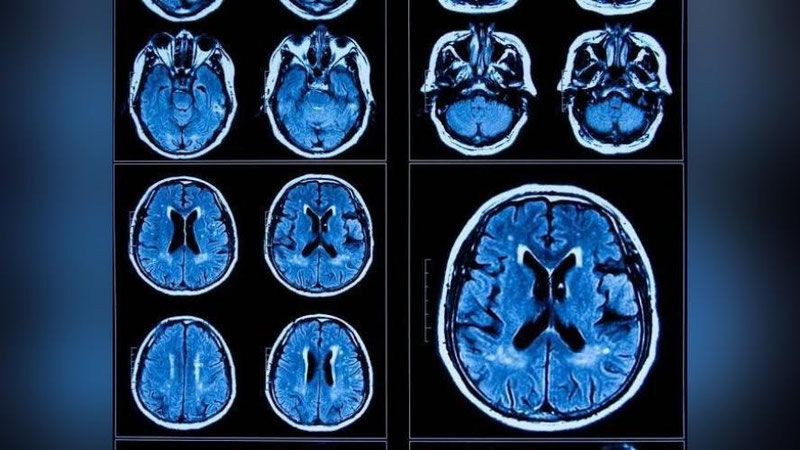

Otopsiyalar natijasida kasallikning miyada ko`rsatgan ta`sirlari qarishga o`xshashligi kuzatildi. Tadqiqot mualliflari, o`z ishlarini COVID-19'ni miya qarishining molekulyar ishoralariga bog`lagan ilk tadqiqot ekanligini ma`lum qildi.

Yigirma yoshdan to sakson yoshgacha bo`lgan ko`ngillilar guruhi, COVID-19'ning og`ir shaklidagi 21 kishi, asemptomatik ko`rinishidagi 1 kishi va umuman infeksiya yuqtirmagan 22 kishidan iborat bo`ldi. Prefrontal korteks namunalarini RNK ketma-ketlik texnologiyasi bilan tekshirgan olimlar, COVID-19'ning og`ir ko`rinishini boshdan kechirgan bemorlarda qarish bilan bog`liq genetik ifodasida ortish yuzaga kelganini guvohi bo`ldi.

Tadqiqot natijalariga ko`ra, immunitet bilan bog`liq gen ifodasi COVID-19'ning og`ir ko`rinishidagi bemorlarda keksalarda bo`lgani kabi kamayadi. Shuningdek, sinaptik faollik, kognitiv funksiyalar va xotira bilan bog`liq genlarning ifodasida keksalardagi kabi kamayish kuzatilgan.